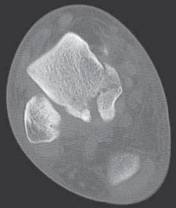

The type I fracture is nondisplaced. Disruption of blood flow is limited to the anterolateral region of the bone. I recommend a computed tomography (CT) scan to confirm no displacement of the fracture before diagnosing a type I fracture. Historically, Hawkins reported a 13% incidence of osteonecrosis in type I injuries ( FIG 1A).

In the type II talar neck fracture there is displacement of the talar dome fragment, which is routinely posterior, often depicting clear subluxation of the talar body. Blood flow to the medial body and head is preserved. The type II talar neck fracture has a 20% to 50% risk of avascular necrosis ( FIG 1B). 697

A B C

FIG 1 • Hawkins classification of talar fractures. A. Type I: disruption of anterolateral perfusion. B. Type II: medial perfusion intact. C. Type III: all D sources of blood flow injured. D. Type IV: dislocation of all articulations. 1. In the type III injury, the transverse fracture of the talar neck is associated with dislocation of the talar body. The incidence of osteonecrosis of the talar body is 50% to 100%. All major perfusion to the body of the talus is damaged ( FIG 1C). 2. A type IV injury of the talar neck has been documented; it is a type III fracture-dislocation with associated talonavicular dislocation.2 All extraosseous blood flow to the talus is considered disrupted. The value of the Hawkins classification is that it allows the orthopedic surgeon to predict what to expect with a specific talar neck injury. Open reduction and rigid internal fixation is the recommended treatment ( FIG 1D). 1. Talar body fractures are defined as fractures extending into or posterior to the lateral process. PATIENT HISTORY AND PHYSICAL FINDINGS 2. Fractures of the talus are commonly associated with vehicular trauma and falls. 1. The relationship of severe lower extremity trauma and airbags is well known. After airbag deployment, the torso and lower extremities are directed toward the floor panel of the car. 2. I believe that the incidence of high-energy hindfoot trauma will increase over time. Globally, transport related injuries remain the leading cause of disability from injury. By 2020, traffic injuries will increase from a current 9th position to 3rd disability-adjusted life years lost. 3. The history and the clinical status of the talar injury must be carefully recorded because the injury severity is likely to correlate with the long-term patient outcome. 1. On the initial examination the physician should note pain, motion, crepitus, deformity, soft tissue swelling, open fractures, and associated fractures of adjacent bones to the foot and ankle and should perform a complete neurovascular evaluation of the extremity. 4. Detailed documentation of the talus fracture pattern and local soft tissue injury is paramount. 1. Soft tissue local pressure phenomenon, commonly found anterolaterally in closed type III fractures of the talar neck, may precipitate full-thickness pressure necrosis of the skin if not decompressed early. 2. Severe swelling of the ankle is common in the acute fracture of the talus and may progress to fracture blister formation, precluding safe execution of operative incisions. 5. The physician should examine the skin for swelling, ecchy-mosis, fracture blisters, and deformity; these are signs of a closed fracture. 1. A closed injury with mild or moderate swelling (bony landmarks palpable) indicates talar neck type I and II fractures and process fractures. 2. A closed injury with severe swelling indicates talar neck type III and IV fractures and body fractures. 6. Open fractures will be apparent by the transverse, medial, or supramalleolar traumatic laceration of the ankle. Lateral, posterior, and plantar wounds are uncommon. 7. The physician should perform vascular, neurosensory, and myotendinous examinations of the foot and ankle. IMAGING AND OTHER DIAGNOSTIC STUDIES 8. Three plain radiographic views are necessary to radiographi-cally evaluate talus fractures: anteroposterior (AP), mortise (15-degree internal rotation view), and lateral images of the ankle. 1. The AP and mortise views of the ankle demonstrate alignment of the talar body in the ankle mortise. The lateral view depicts the sagittal outline of the talus. 9. The Canale view is used to assess varus or valgus malalignment of the talar neck, particularly with Hawkins type I and II injuries. The knee must be flexed and the foot in equinus and everted, with the x-ray tube directed 15 degrees caudad ( FIG 2A).